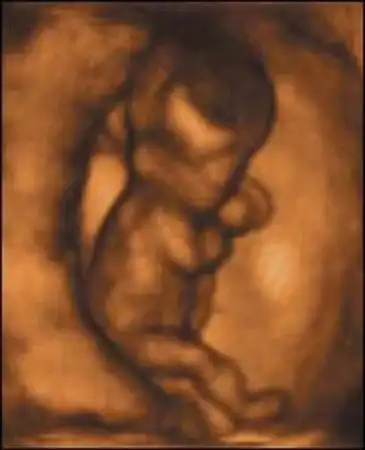

16-я неделя. Появляются брови и ресницы, образовались суставы, началось затвердение костей. Уже можно распознать пол ребенка, хотя на УЗИ это удается не всегда.

20-я неделя. На голове появляются волосы, формируются зубы. Ребенок активно двигается, может реагировать на внешние звуки. Он уже большой (25 см), но очень худенький – весит 340 г.

24-я неделя. Ребенок прибавил в весе до 540 г. И в росте – 33 см. Образуются потовые железы. Малыш может кашлять и икать, что ощущается мамой, как легкое постукивание. Он слышит голоса и музыку, реагирует на них возбуждаясь или успокаиваясь.